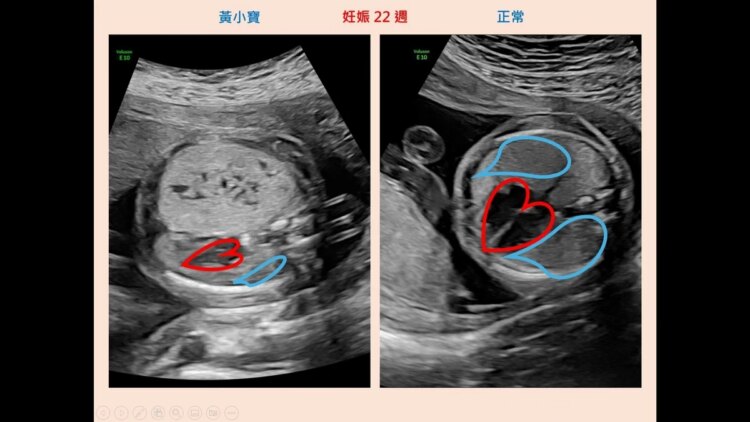

28歲黃女士在懷孕22週時,因產檢發現胎兒肺部腫瘤,轉診至台北榮總,經高層次超音波檢查發現,胎兒右肺有3公分的先天性肺部呼吸道畸形(CPAM)並擠壓心臟。醫師指出,CPAM大部分可在產檢時發現,但不同病人的病灶表現及病情差異大,嚴重可能須手術治療,由於該名胎兒未發現其他器官異常情形,經與醫療團隊討論後,黃女士決定繼續懷孕。

台北榮總婦女醫學部高危險妊娠暨產科主任葉長青表示,肺部呼吸道畸形(CPAM)為先天性肺部發育異常,是指胎兒的肺葉被沒有功能的囊腫組織取代,發生率約為4,500~11,000之一,是最常見的胎兒肺部腫瘤。

葉長青進一步指出,CPAM的嚴重程度隨病灶之大小、位置及衍生症狀而異,若病灶不大,隨著孕程進展,約有50%的腫瘤可能自發性縮小,出生後若無症狀追蹤即可。若病情無好轉,可能造成胎兒水腫,一出生就須接受手術治療。罕見遇到病情嚴重者,有危及胎兒生命、需終止懷孕的風險。

負責切除肺腫瘤的兒童外科權威、台北榮總移植外科主任兼任兒童外科主治醫師劉君恕表示,胎兒發現肺腫瘤時直徑只有3公分,到了懷孕後期已達7公分,腫瘤體積更是原先的8倍大,佔據肺部超過70%,對心肺持續壓迫,「最棘手的地方在於,因此造成胎兒水腫、腹水以及羊水過多,並導致子宮收縮與早產現象,危及胎兒生命。」